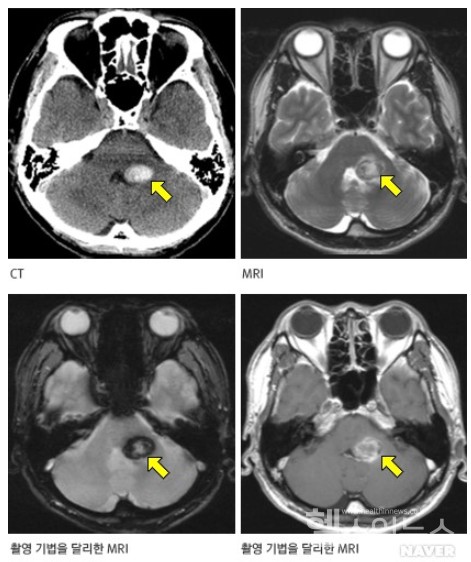

해면상 혈관종은 뇌, 척수, 간, 피부 등에 발생하는 혈관 기형입니다. 해면상 혈관종은 혈관의 내피세포가 비정상적으로 증식해 혈관이 비정상적으로 확장된 것입니다. 해면상 혈관종은 뇌에 가장 많이 발생하고, 뇌에 발생하는 경우 뇌출혈, 발작, 두통 등의 증상을 유발할 수 있습니다.

해면상 혈관종은 뇌에 가장 많이 발생하는 혈관 기형으로, 뇌출혈, 발작, 두통 등의 증상을 유발할 수 있습니다. 해면상 혈관종의 증상이 나타나면 즉시 병원을 방문해 적절한 치료를 받는 것이 중요합니다.